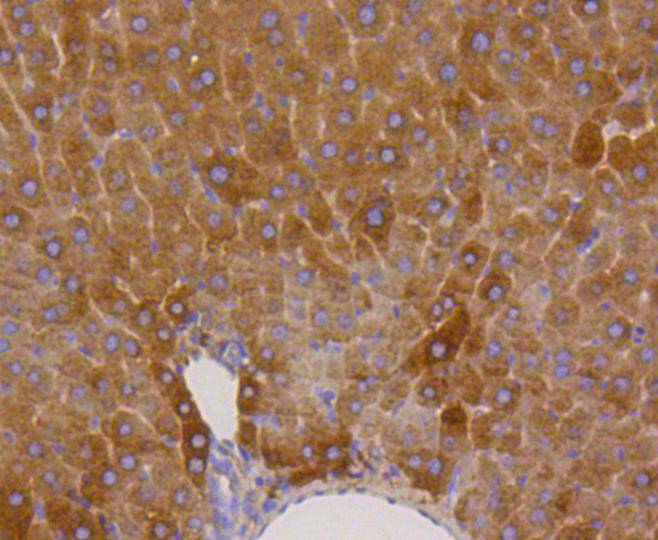

Immunohistochemical analysis of paraffin-embedded mouse liver tissue using anti-Phospho-Glycogen synthase 1(S641) antibody. Counter stained with hematoxylin.